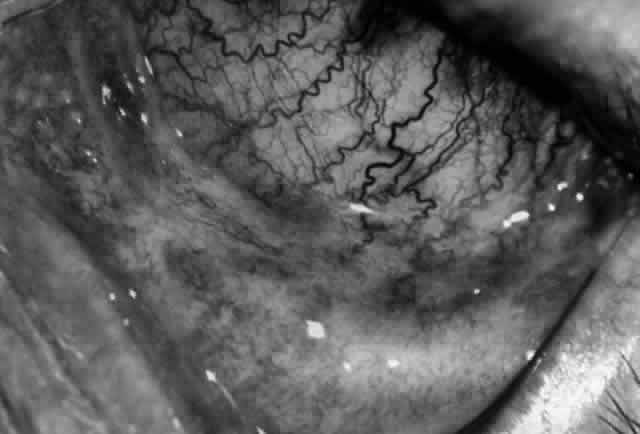

Clinically, the ocular disease in cicatricial pemphigoid (OCP) may present unilaterally in the form of a chronic, recurrent catarrhal conjunctivitis, but it eventually becomes bilateral. Subepithelial fibrosis is characteristic of stage 1 of OCP (Fig. 7). Stage 2 shows fornix foreshortening (Fig. 8), and symblepharon formation is the hallmark of stage 3 (Fig. 9). Stage 4, end-stage disease, is characterized by ankyloblepharon and surface keratinization (Fig. 10). Obstruction of the lacrimal ductules and meibomian gland ducts eventually produces an unstable tear film and progressive sicca syndrome, but it is to be emphasized that OCP is not a dry-eye syndrome until late in the disease course.20 Trichiasis and entropion occur because of the subepithelial fibrosis, with eventual keratopathy, corneal neovascularization, and corneal ulceration and scarring.20

Fig. 7. Stage 1 cicatricial pemphigoid, with cicatrizing conjunctivitis, and fine striae-type areas of subepithelial fibrosis, but without evidence of shrinkage of the conjunctiva.